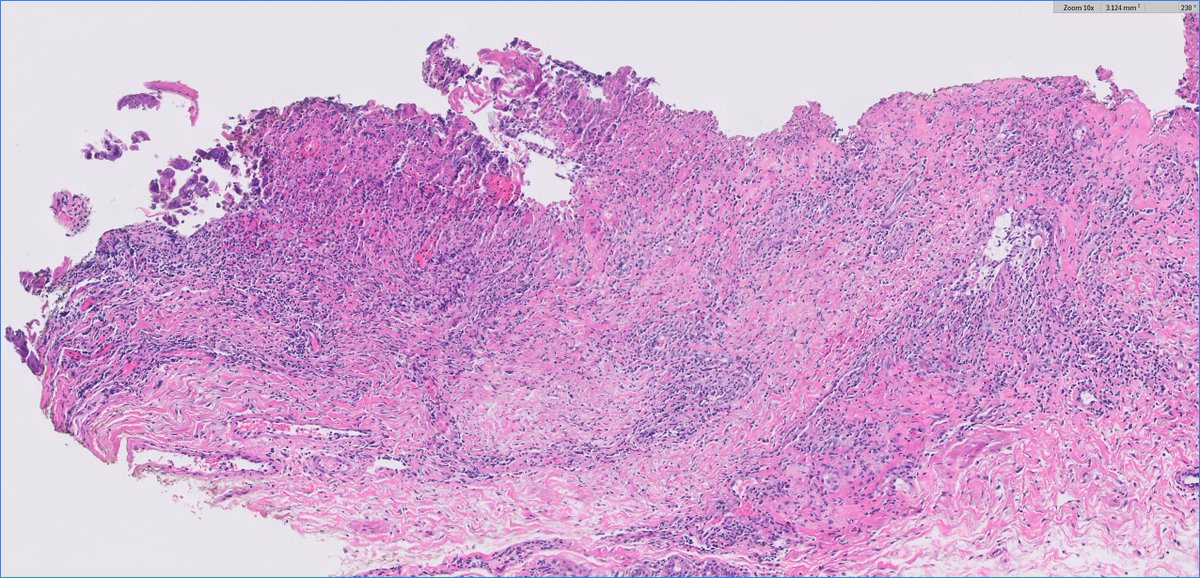

#Breastpath #Surgpath #Pathresidents #Pathtwitter Resection of a suspicious breast mass in a 60 year old woman. Take a look at some images, place your vote, and read some discussion.

BrownPathology's tweet image. #Breastpath #Surgpath #Pathresidents #Pathtwitter

Resection of a suspicious breast mass in a 60 year old woman.  Take a look at some images, place your vote, and read some discussion.